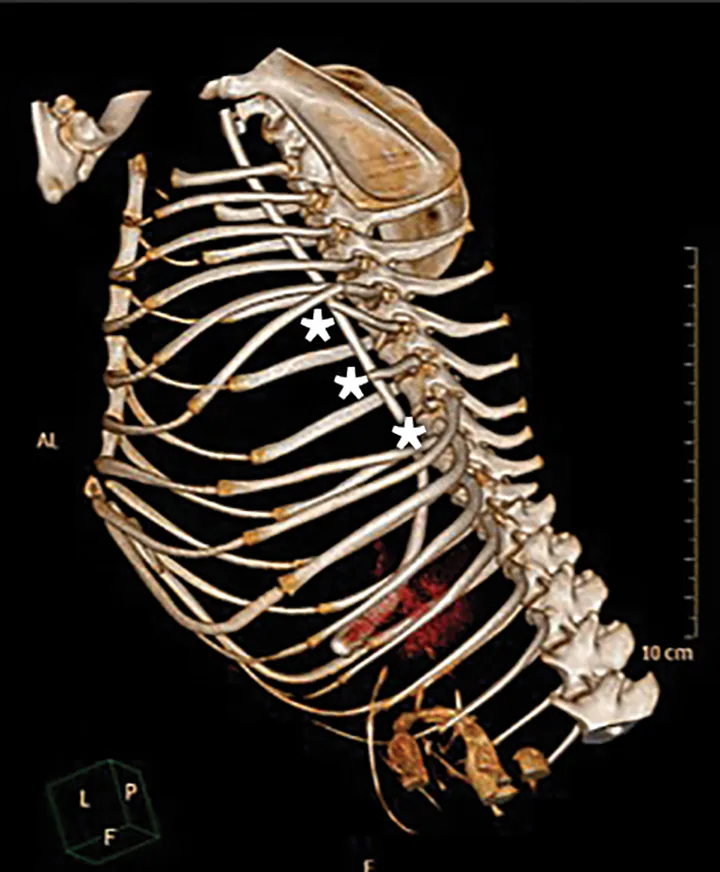

CT scans can provide more specific information about the extent of the injuries (Figure 2); however, CT requires deep sedation or general anesthesia, which limits its use in patients with marked respiratory distress.6

CT reconstruction of the thoracic skeleton of a 4-year-old female dachshund with apparent left-sided flail chest after an attack by another dog. The patient suffered a combination of proximal single and segmental fractures and luxations of ribs 6 through 11 on the left side (asterisks). Severe displacement of the ribs, along with extensive soft-tissue trauma, permitted paradoxical motion of the thoracic wall soft tissue.